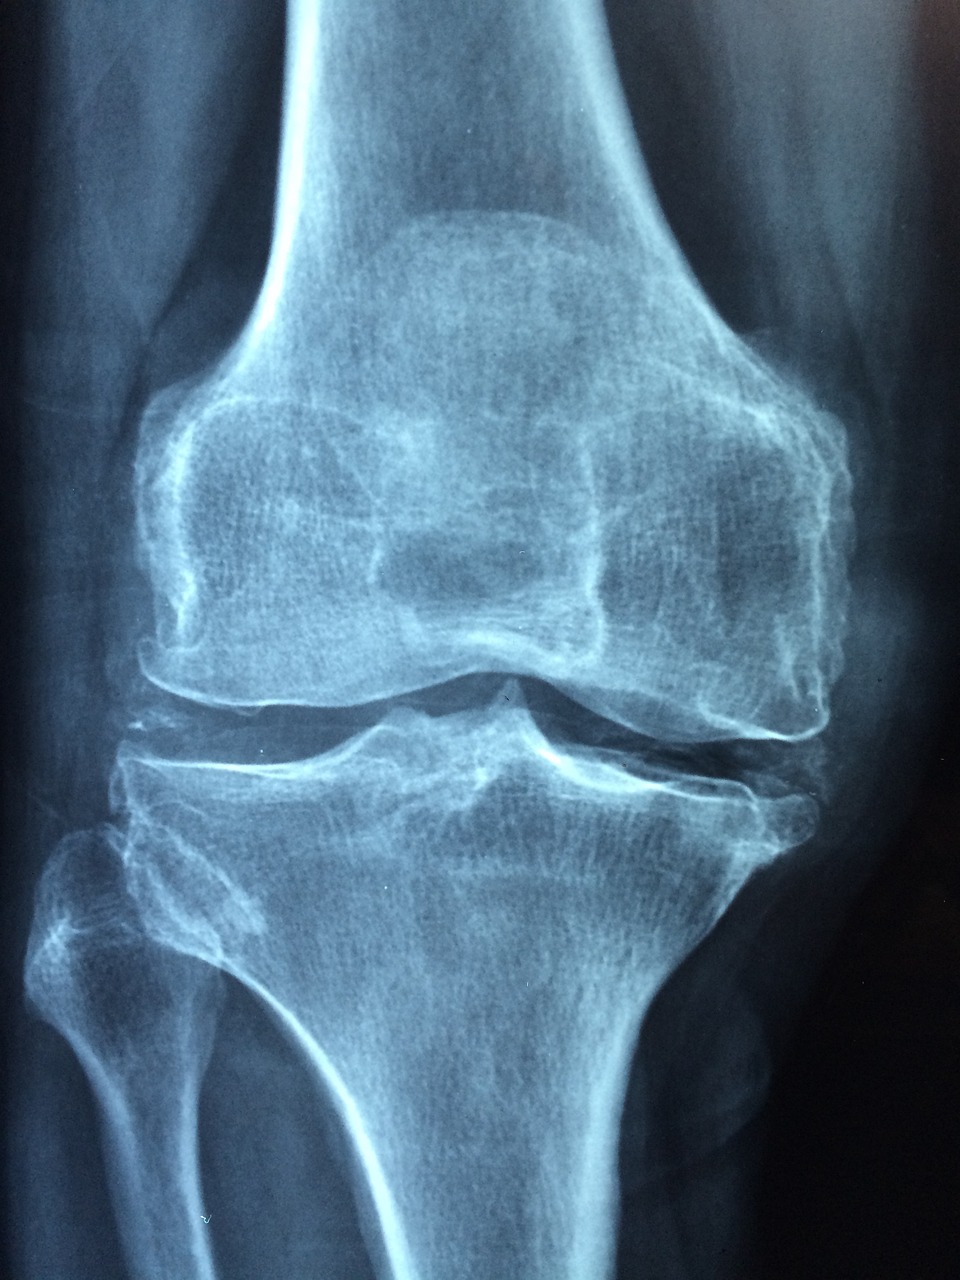

골다공증은 점진적인 골량 손실과 골 조직의 악화를 특징으로 하는 의학적 상태로, 그 결과 뼈가 약해지고 부서지기 쉽습니다. "골다공증"이라는 용어는 말 그대로 "다공성 뼈"를 의미합니다. 골다공증 환자의 경우 골밀도가 감소하여 약간의 스트레스나 외상에도 뼈가 골절되기 쉽습니다. 이 상태는 일반적으로 천천히 진행되며 종종 골절이 발생할 때까지 눈에 띄지 않습니다. 골다공증 환자의 일반적인 골절 부위에는 척추(척추 골절), 엉덩이(엉덩이 골절), 손목 및 갈비뼈가 있습니다. 골다공증은 신체가 오래된 뼈를 제거하는 속도와 일치하는 속도로 새로운 뼈를 형성하지 못할 때 발생합니다. 이러한 불균형은 정상적인 뼈 리모델링 과정을 방해하여 시간이 지남에 따라 뼈 질량의 순 손실을 초래합니다.

골다공증 증상엔 크게 3가지로 볼 수 있는데 요통과 키 손실, 그리고 골절입니다. 요통은 특히 척추의 골다공증 관련 골정로 만성 또는 급성 요통을 유발할 수 있습니다. 또한 키 손실을 가져올 수 있으며 가장 무서운건 골절이 쉽게 일어납니다.

50세 이상의 폐경 후 여성의 경우 폐경기 동안 중요한 여성 호르몬의 감소로 인해 골다공증 관련 골절이 발생할 위험이 높아집니다. 가장 일반적으로 영향을 받는 부위는 척추, 근위 대퇴골(엉덩이) 및 손목입니다. 이 중 대퇴골 근위부(엉덩이)의 골절이 가장 많이 발생하여 흔히 발생합니다. 고관절 골절이 발생하면 향후 신체의 다른 부위에 골다공증성 골절이 발생할 가능성이 높아집니다. 따라서 이러한 골절의 징후를 경계하고 적절한 조치를 취하는 것이 중요합니다. 골다공증은 초기에 눈에 띄는 증상을 나타내지 않기 때문에 소리 없는 질병으로 여겨지는 경우가 많습니다. 결과적으로 많은 사람들이 골절을 경험할 때까지 자신의 상태를 인식하지 못합니다. 따라서 골밀도 검사를 통한 조기 발견과 적절한 관리 전략은 골절을 예방하고 뼈 건강을 유지하며 전반적인 삶의 질을 향상시키는 데 중요합니다.